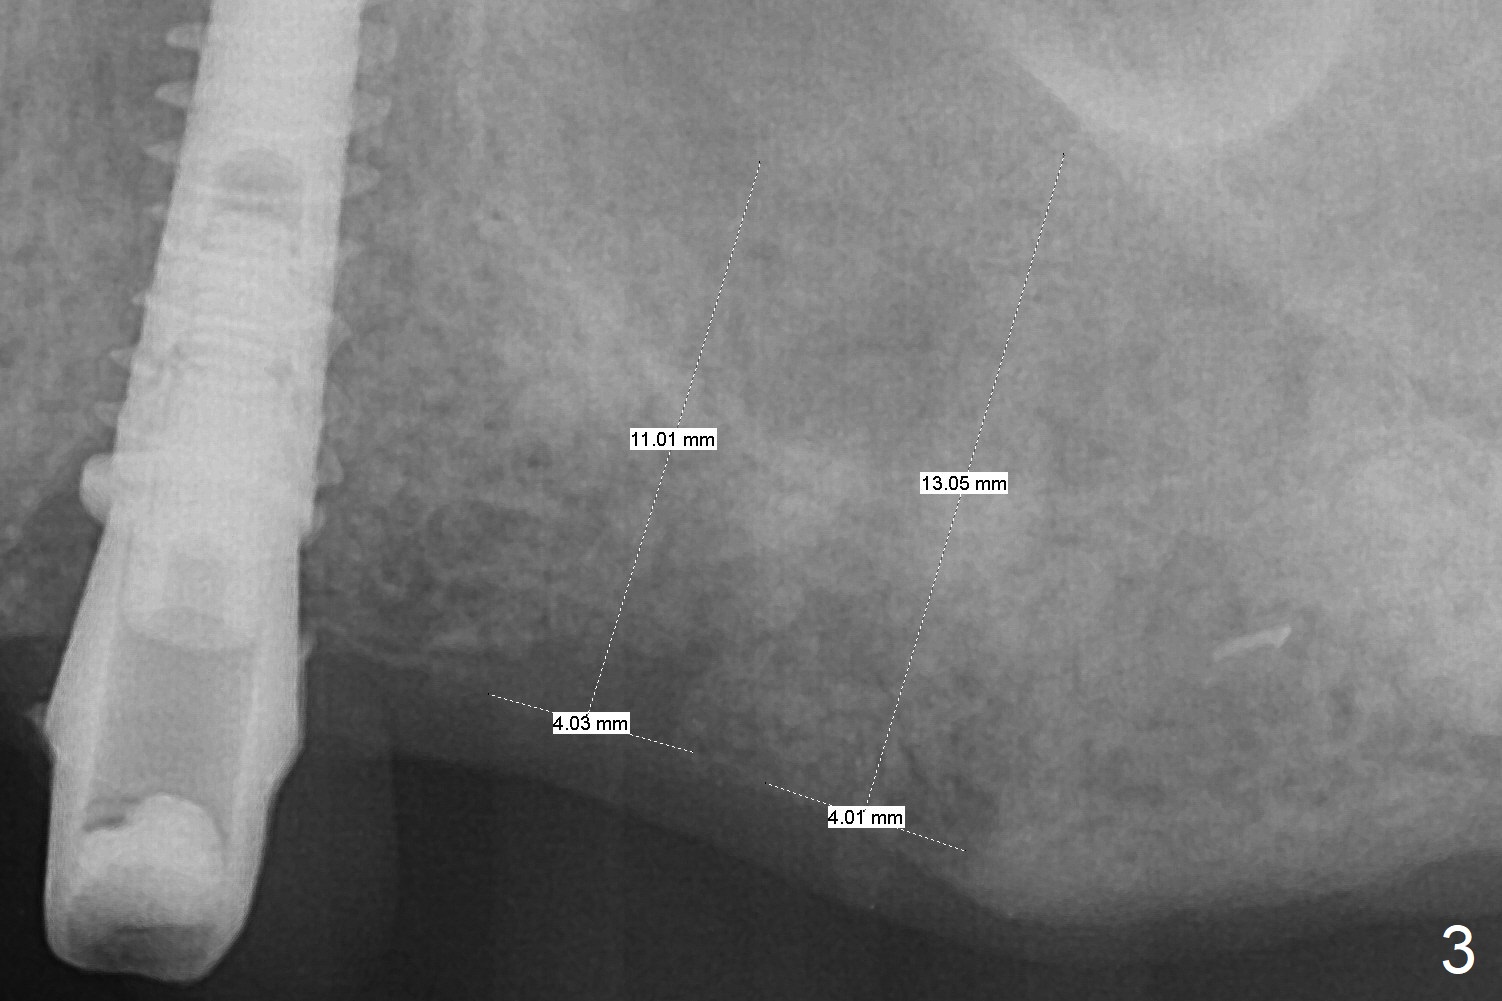

A 73-year-old man lost #15 implant 4 months ago with socket preservation (Fig.1 (taken 1 month post bone graft (^)). The tooth #14 was extracted with socket preservation ~ 9 months ago. The sites should be not so dense that Magic Split will be used to start osteotomy for 7 mm (Fig.2). Prior to this step, use 1.5 mm or starter drill and surgical stent to mark the initial osteotomy. BEB is followed by Magic Expanders (1 mm longer each). Implants are expected to be 9 or 11 mm long (Fig.3,4).